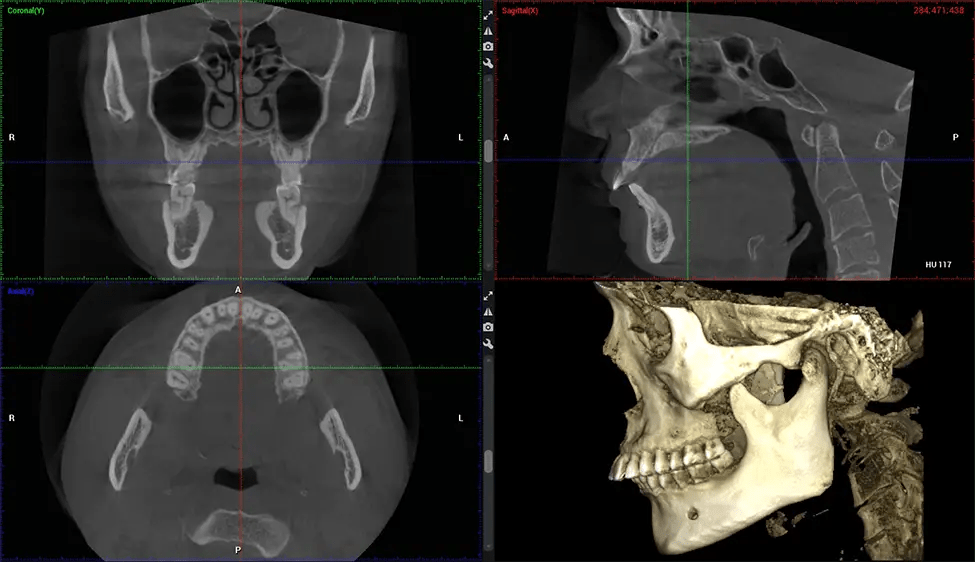

This 3D scan, called cone beam computed tomography, gives your dentist a more complete image of your oral anatomy and disease processes than a traditional X-ray. Unlike conventional X-rays, which capture a 2D image of your mouth from various angles, a 3D scan takes multiple digital X-rays for one image. It provides a complete view of your jaw, teeth, nerves, and soft tissues. This enhanced view allows dentists to detect minor issues not visible in traditional 2D scans, such as impacted wisdom teeth or bone fractures in the sinus cavity.

There are many benefits to using CBCT technology, especially compared to the traditional 2D X-ray format. One of the most significant advantages of CBCT scans is that they provide much more information than traditional X-rays. A scan lets your dentist see images from all angles of your jaw and mouth, including your sinuses, nasal cavity, cheekbones, and other surrounding areas. This added information helps your dentist craft a comprehensive treatment plan that addresses all aspects of your oral health.

Another significant benefit is that 3D imaging provides more precise images of your bone structure. These images are more detailed, providing you with a more accurate diagnosis. An accurate diagnosis means better treatment for you.

Planmeca Viso G7 CBCT ( Cone Beam CT Scan ) is designed to surpass the demands of industry leaders, specialists, and large institutions. It’s has a large ø25×30 cm sensor with four built-in cameras. It can capture unlimited volume sizes from a ø3×3 cm to a ø30x30cm volume capturing the skullcap through C7 on the cervical spine. The Planmeca Viso G7 offers the industry’s largest single volume scan of ø30×19 cm. It’s poised to handle advanced imaging modalities such as Planmeca ProFace® and Planmeca 4D™ Jaw Motion technology. The occipital head support allows an unimpeded view of facial tissue.